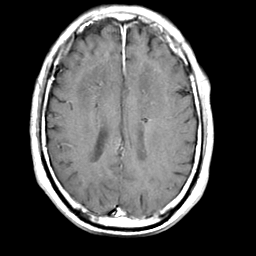

Meningioma, MR Study #2 -- Slice #13

[Home][Help][Clinical] Slice 13